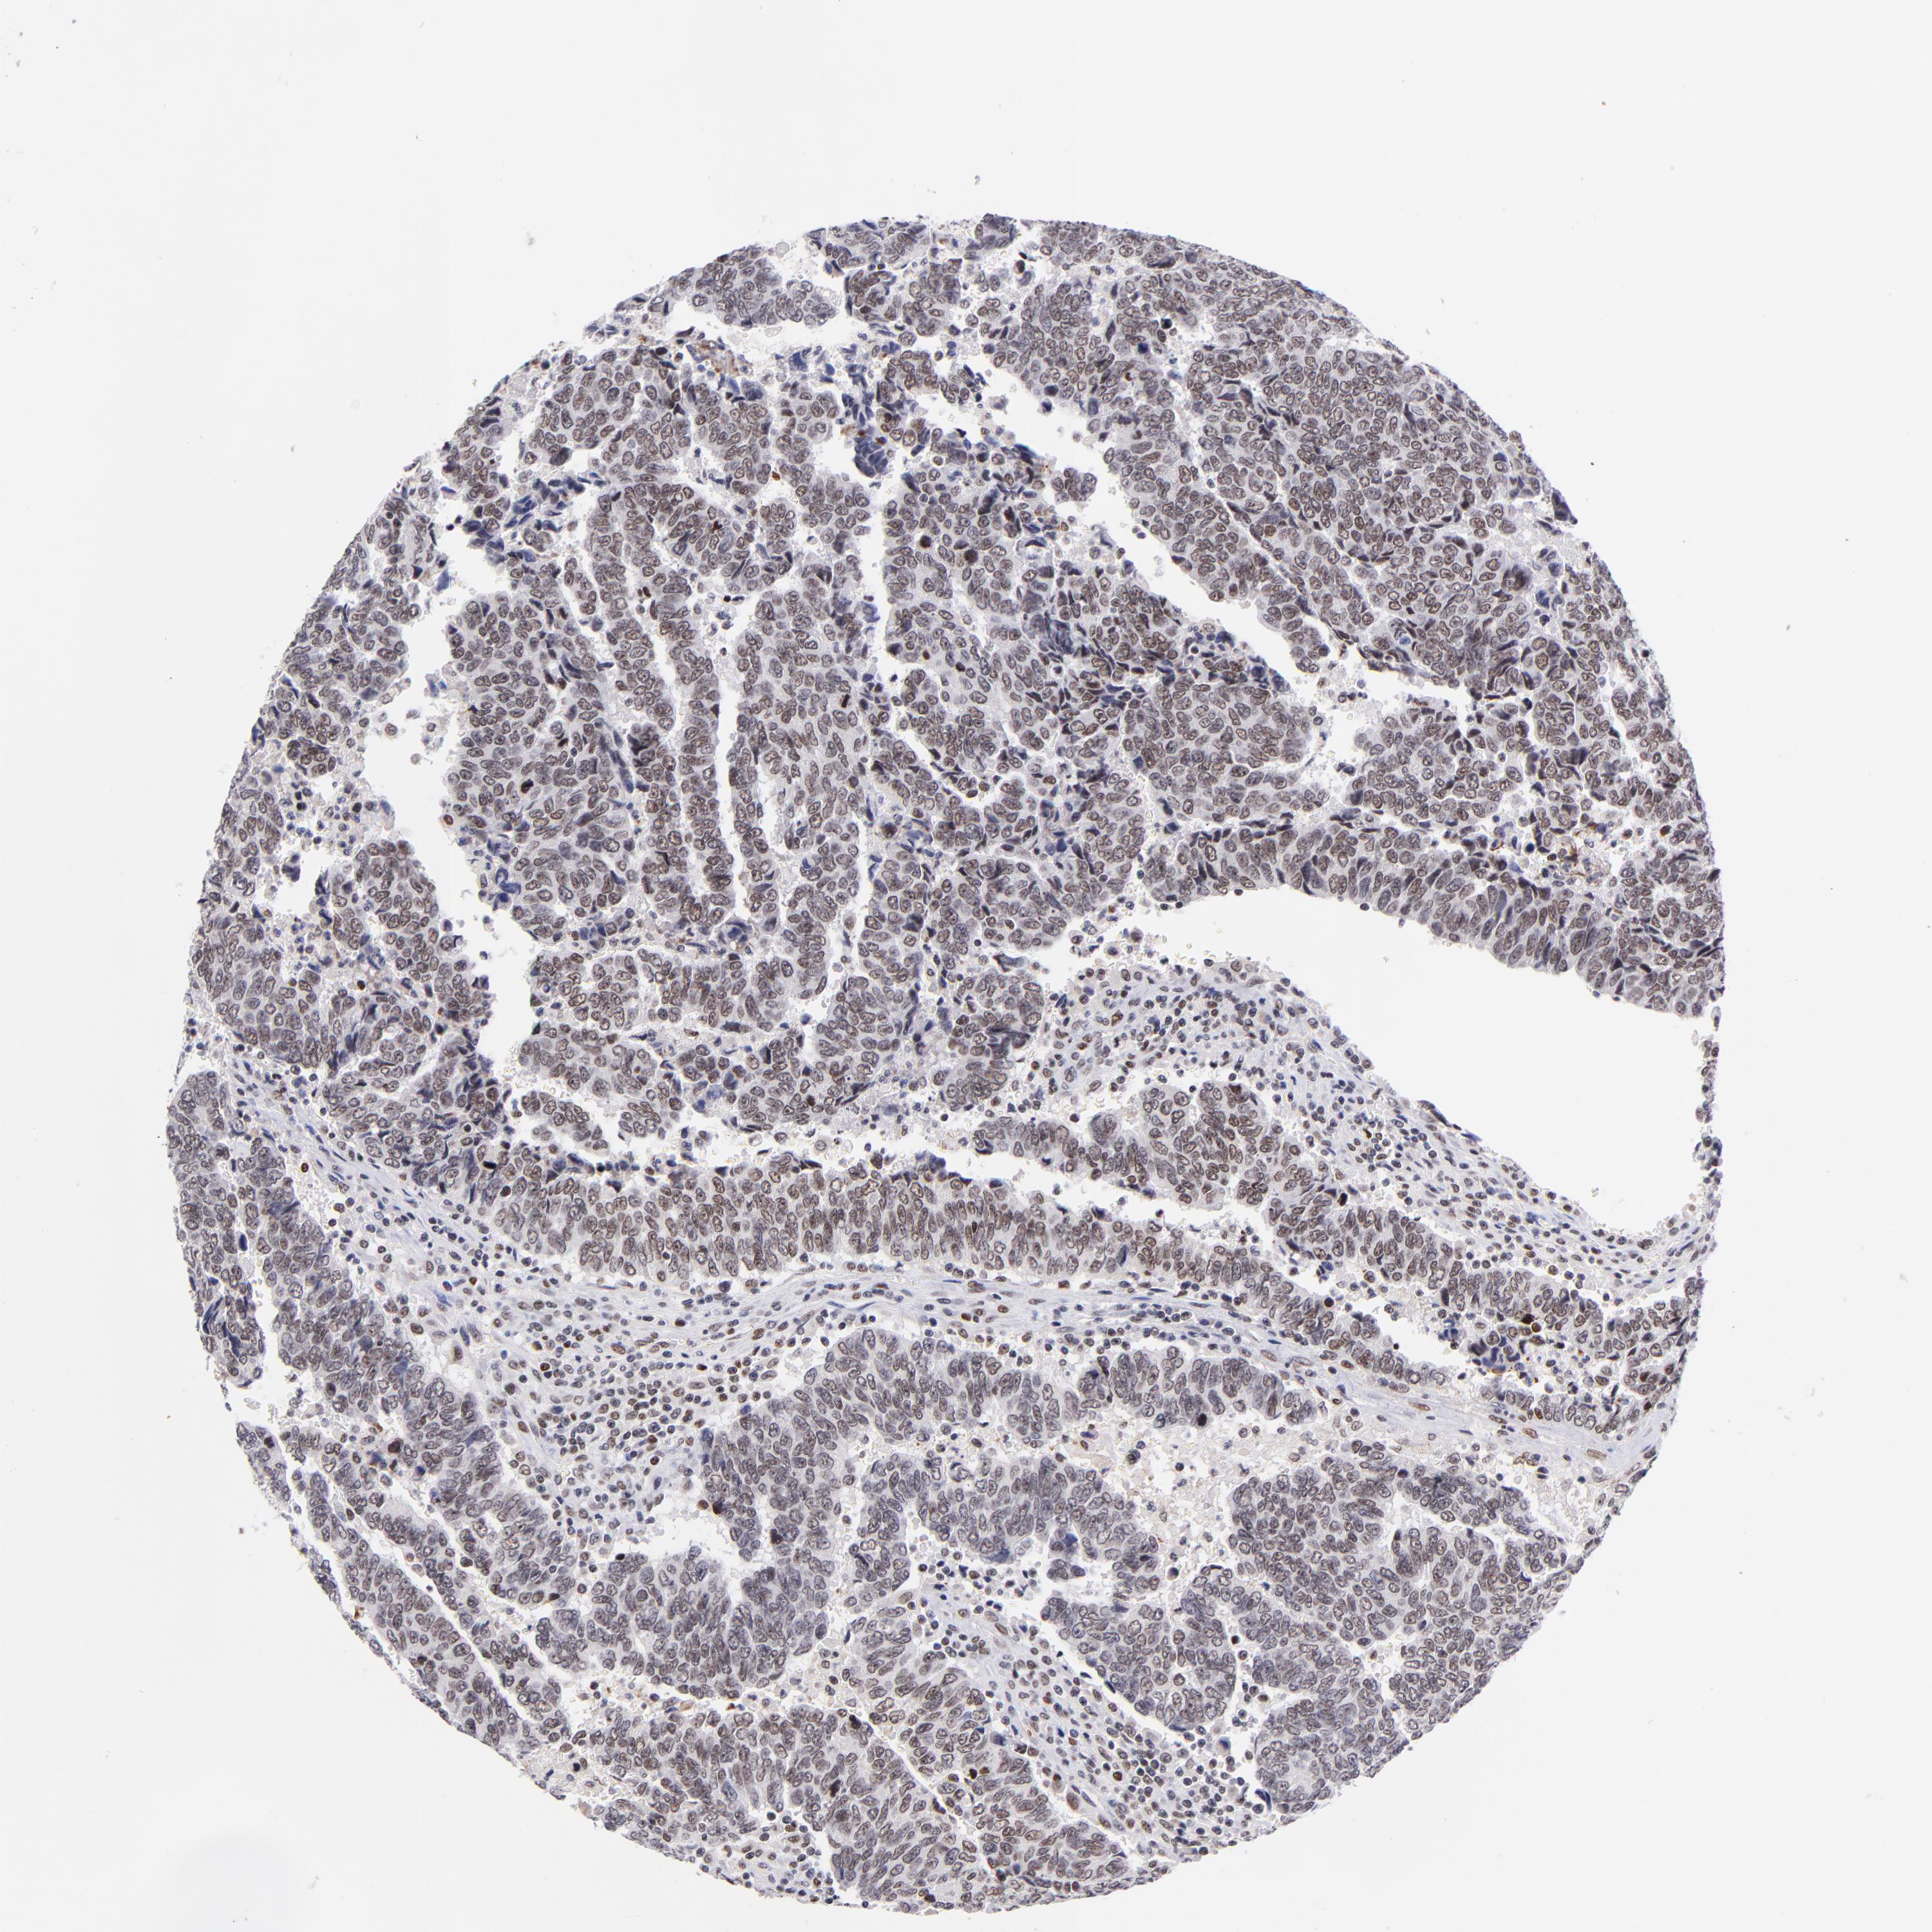

UROTHELIAL CANCER - Protein expressioni

A mouse-over function shows sample information and annotation data. Click on an image to view it in a full screen mode. Samples can be filtered based on level of antibody staining by selecting one or several of the following categories: high, medium, low and not detected. The assay and annotation is described here.

Note that samples used for immunohistochemistry by the Human Protein Atlas do not correspond to samples in the TCGA dataset.

Antibody stainingi

Antibody staining in the annotated cell types in the current human tissue is reported as not detected, low, medium, or high, based on conventional immunohistochemistry profiling in selected tissues. This score is based on the combination of the staining intensity and fraction of stained cells.

Each image is clickable and will lead to virtual microscopy that enables deeper exploration of all samples and also displays staining intensity scores, fraction scores and subcellular localization as well as patient and tissue information for each sample.

Antibody HPA003111

Staining

High

Medium

Low

Not detected

Intensity

Strong

Moderate

Weak

Negative

Quantity

>75%

75%-25%

<25%

None

Location

Nuclear

Cytoplasmic/membranous

Cytoplasmic/membranous,nuclear

Urothelial carcinoma, High grade

Urothelial carcinoma, Low grade